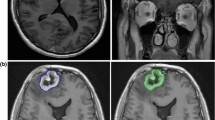

Preoperative clinical MRI scans were performed on commercial 1.0, 1.5 and 3.0 Tesla scanners (Siemens, Erlangen, Germany) utilizing standard RARE T2-weighted, Inversion Recovery FLAIR, and post contrast T1-weighted pulse sequences. Gadolinium chelate contrast agents were administered at standard dose of 0.1 mmol/kg for all patients. Lesion evaluation was performed on a Siemens PACS viewing station, or using eFilm (Merge Healthcare) or Siemens Syngo Imaging on a PC, utilizing standard measurement tools by an experienced neuroradiologist (ALT) who was blinded as to the tumor type, radiosurgery dose and final histopathology. Orthogonal measurements of maximal cross-sectional dimensions and perimeter tracings or elliptical area measurements were generated for each case (see Fig. 2). The maximal cross-sectional area on each imaging modality was utilized to evaluate the lesion quotient.

43 year old woman with metastatic melanoma status-post SRS to the right frontal lobe 2 years prior to imaging to a dose of 18 Gy. Axial MRI demonstrating the two techniques utilized to obtain measurements. On the left, orthogonal diameters are demonstrated on the T2 axial MRI of the lesion at the right frontal lobe (1.7 cm in anteroposterior direction and 1.8 cm in transverse orientation) as well as an ellipsoid measurement of the lesion area, 2.5 cm2. On the right, the same lesion on T1-contrast enhanced axial MRI is assessed with same measurements. In the case of irregular shapes, perimeter tracings were performed by hand in addition to maximal diameter measurements. LQ was 0.63 which predicted radiation necrosis. Histopathology revealed radiation necrosis without evidence of tumor progression